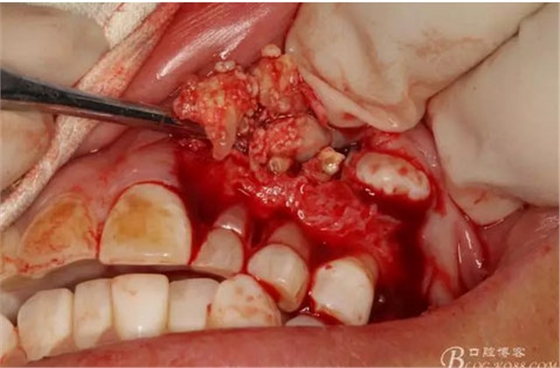

圖15.剝離出來(lái)的多個(gè)成型小牙齒及致密鈣化物。

圖16.形態(tài)各異的小牙齒。